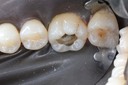

Scott Kanamori #31 prep

Scott Kanamori #31 finish